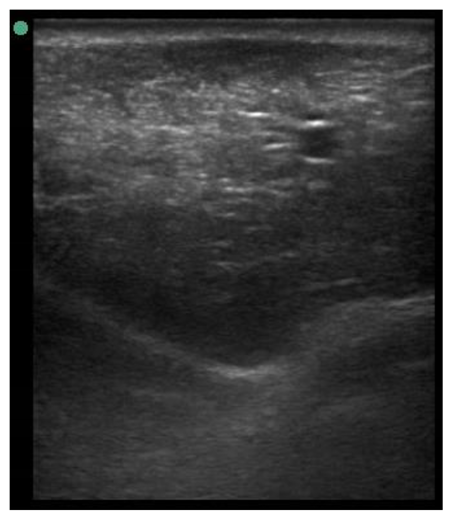

A minimum of three images were taken from each udder half. Images included the gland cistern, mammary parenchyma, putative fat pad and the boundary between the mammary gland and the abdominal wall. One image of suitable resolution per udder half, where all structures were identifiable and present was selected for image processing [27]. Udder halves with an udder palpation score of 4 or 5 (Table 1) at a specific time point (P107, L29 or L100) were considered “abnormal” [23] and were not included in the image selection (heavy: 1 ewe with 1 half and control: 2 ewes with 1 half each).

The image processing was undertaken using ImageJ software [28] as used by Abràmoff et al. [29]. The scales between pixels and millimetres were calculated based on the number of pixels, the scanning depth (mm), and the transducer width (mm) (Figure 4). This method relies on the ability of the operator to interpret and identify lines on the images. To standardize the assessment compartment depth, drawing templates were created for each time point as used by Molenaar et al. [30] and included four representative images from four different yearling ewes with and without the lines drawn for each compartment (Appendix A). The total depth of mammary gland conservative (MTc) was the smallest likely demarcation (abdominal wall) of the mammary gland (Figure 5a), and total depth of the mammary gland generous (MTg) was the largest likely demarcation of the mammary gland visible on the image [30] (Figure 5a). The MTc, MTg, fat pad (FP), parenchyma (PAR), and gland cistern (GC) depths were estimated at the deepest point for each sub-compartment, excluding the skin layers, using the straight tracer (Figure 5a) and were expressed in millimetres.

Figure 5.

(a) Demonstration of delimitations of the mammary total depth conservative (MTc) and generous (MTg), mammary gland cistern (GC), parenchyma (PAR) and the fat pad (FP) and (b) Demonstration of randomly positioning of regions of interest (1, 2, 3) in the parenchyma.